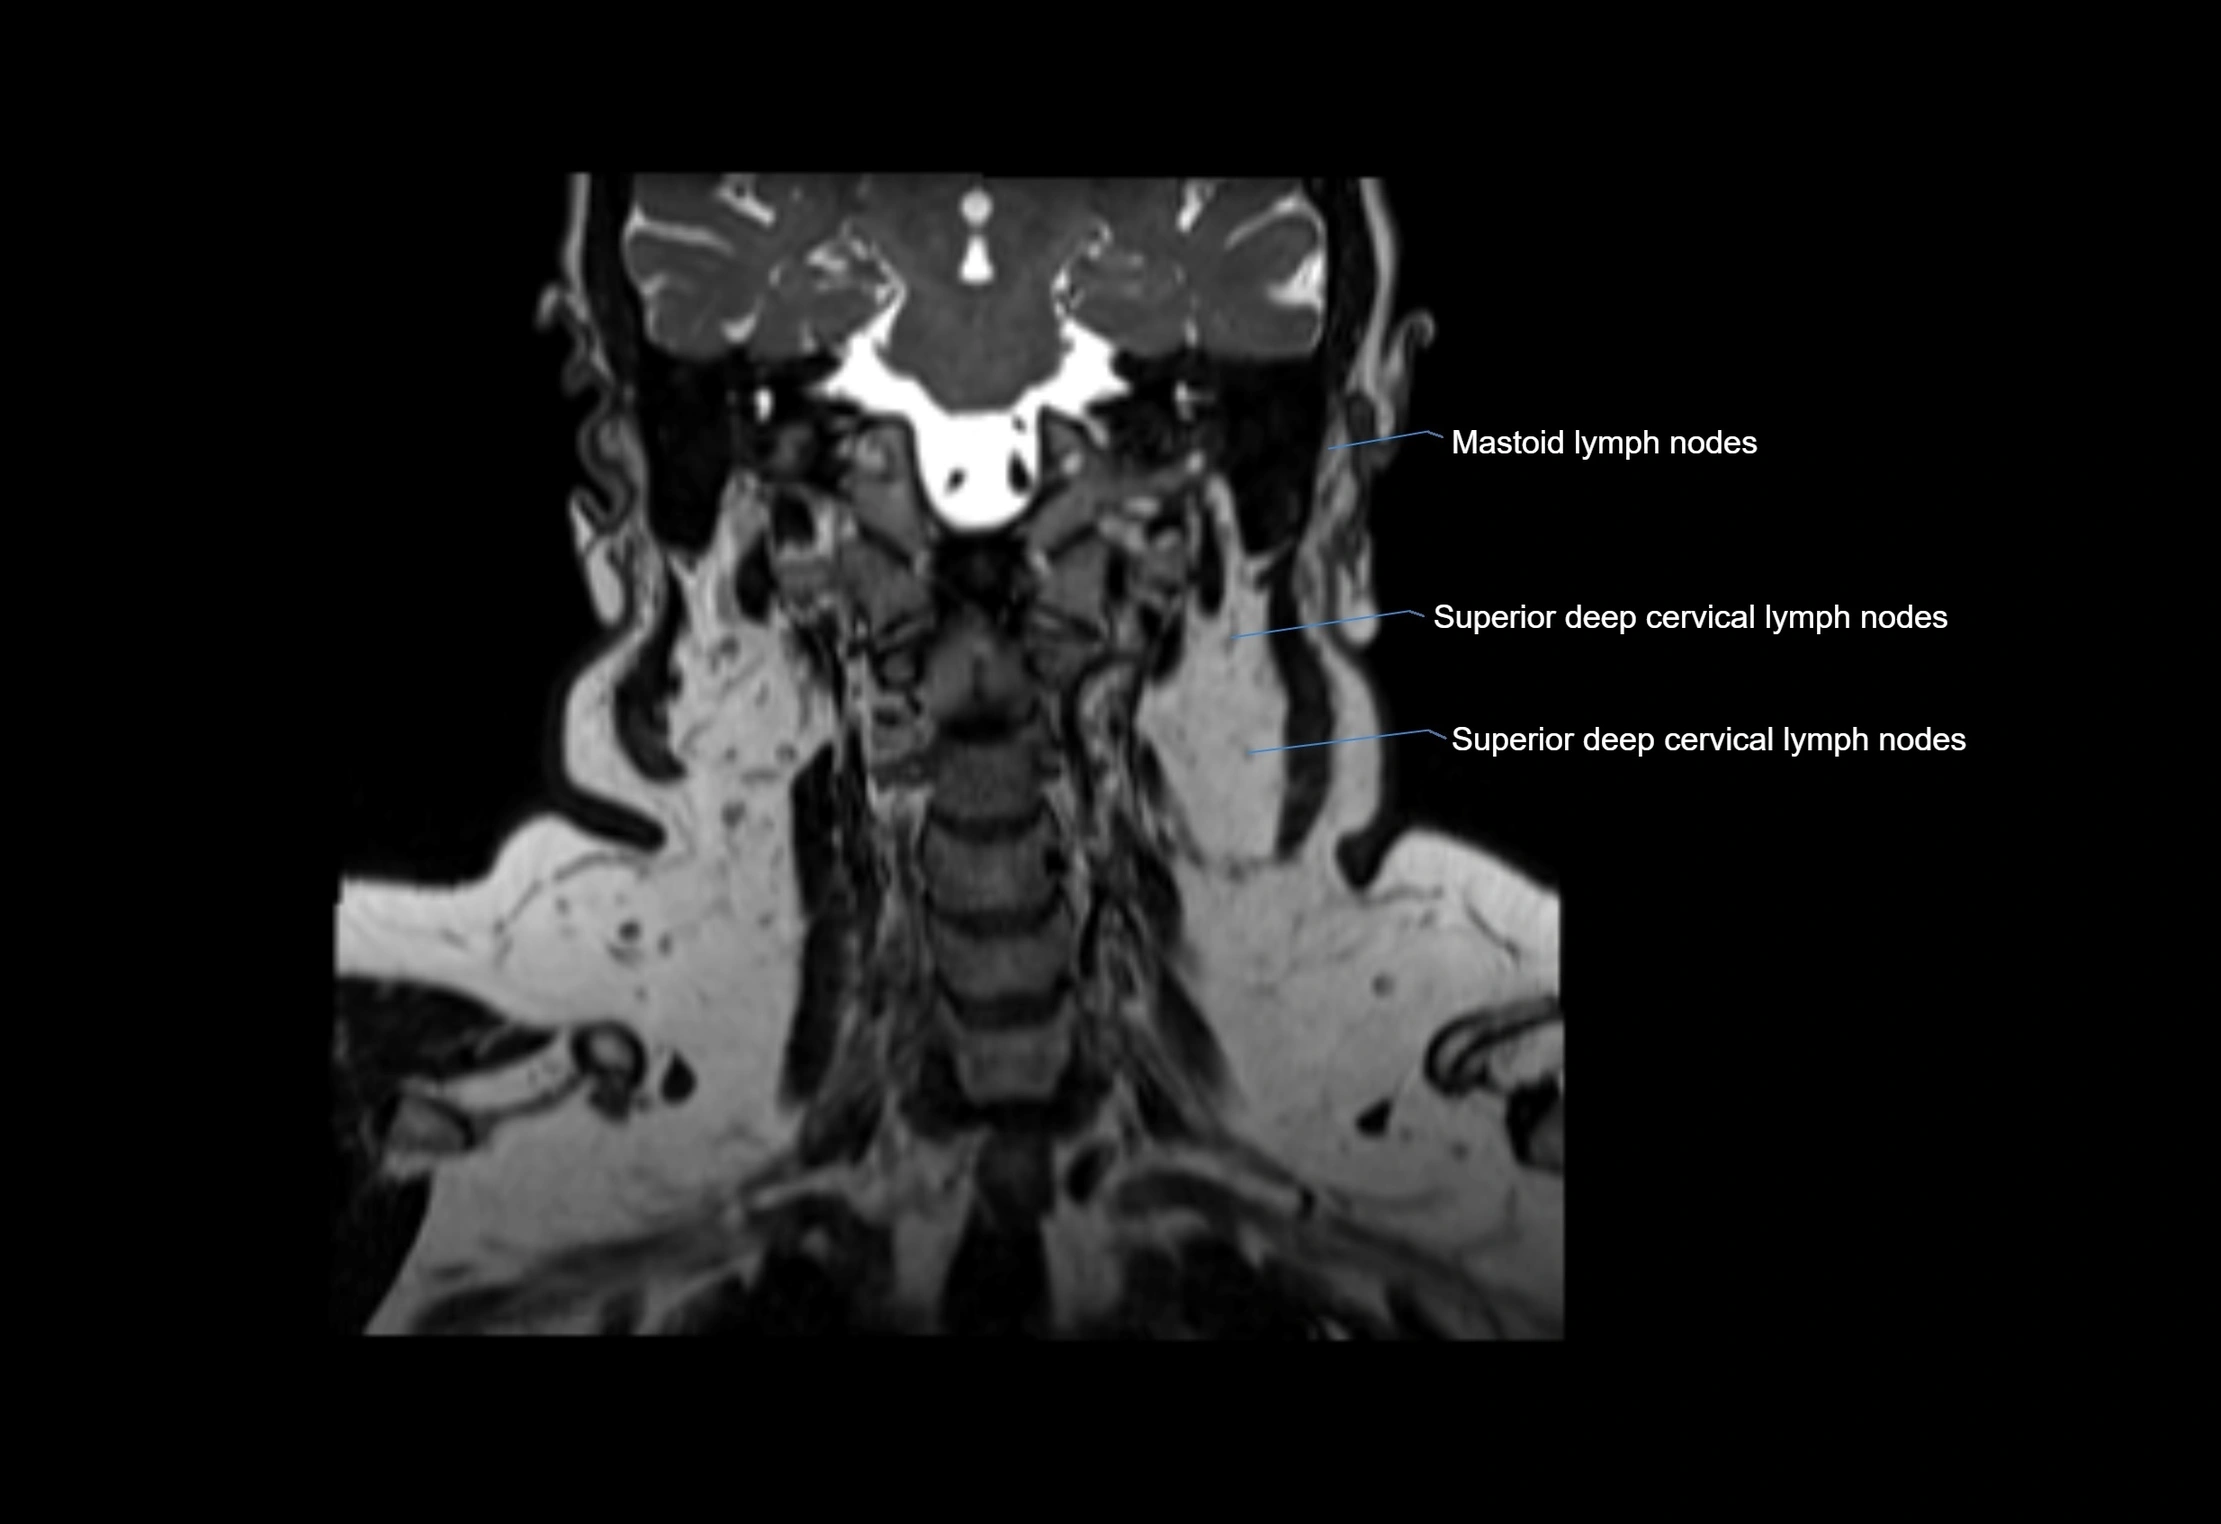

Location

• Found along primary lymph node chains, including preauricular, submandibular, parotid, and occipital regions

• Embedded in subcutaneous fat or superficial fascia, often lateral or posterior to primary nodes

• Variable in number; may occur unilaterally or bilaterally, depending on individual anatomy

MRI Appearance

T1-weighted images:

• Normal accessory nodes appear as small, oval hypointense to intermediate signal structures within subcutaneous fat

• Surrounded by hyperintense fat, enhancing contrast for visualization

• Pathological nodes may appear enlarged or rounded, sometimes with cortical thickening

T1 Post-Contrast (Gadolinium-enhanced):

• Normal nodes may show mild, homogeneous enhancement

• Inflamed or metastatic nodes demonstrate marked homogeneous or heterogeneous enhancement, highlighting the cortex and fatty hilum

• Post-contrast imaging helps detect early metastasis, infection, or inflammatory changes